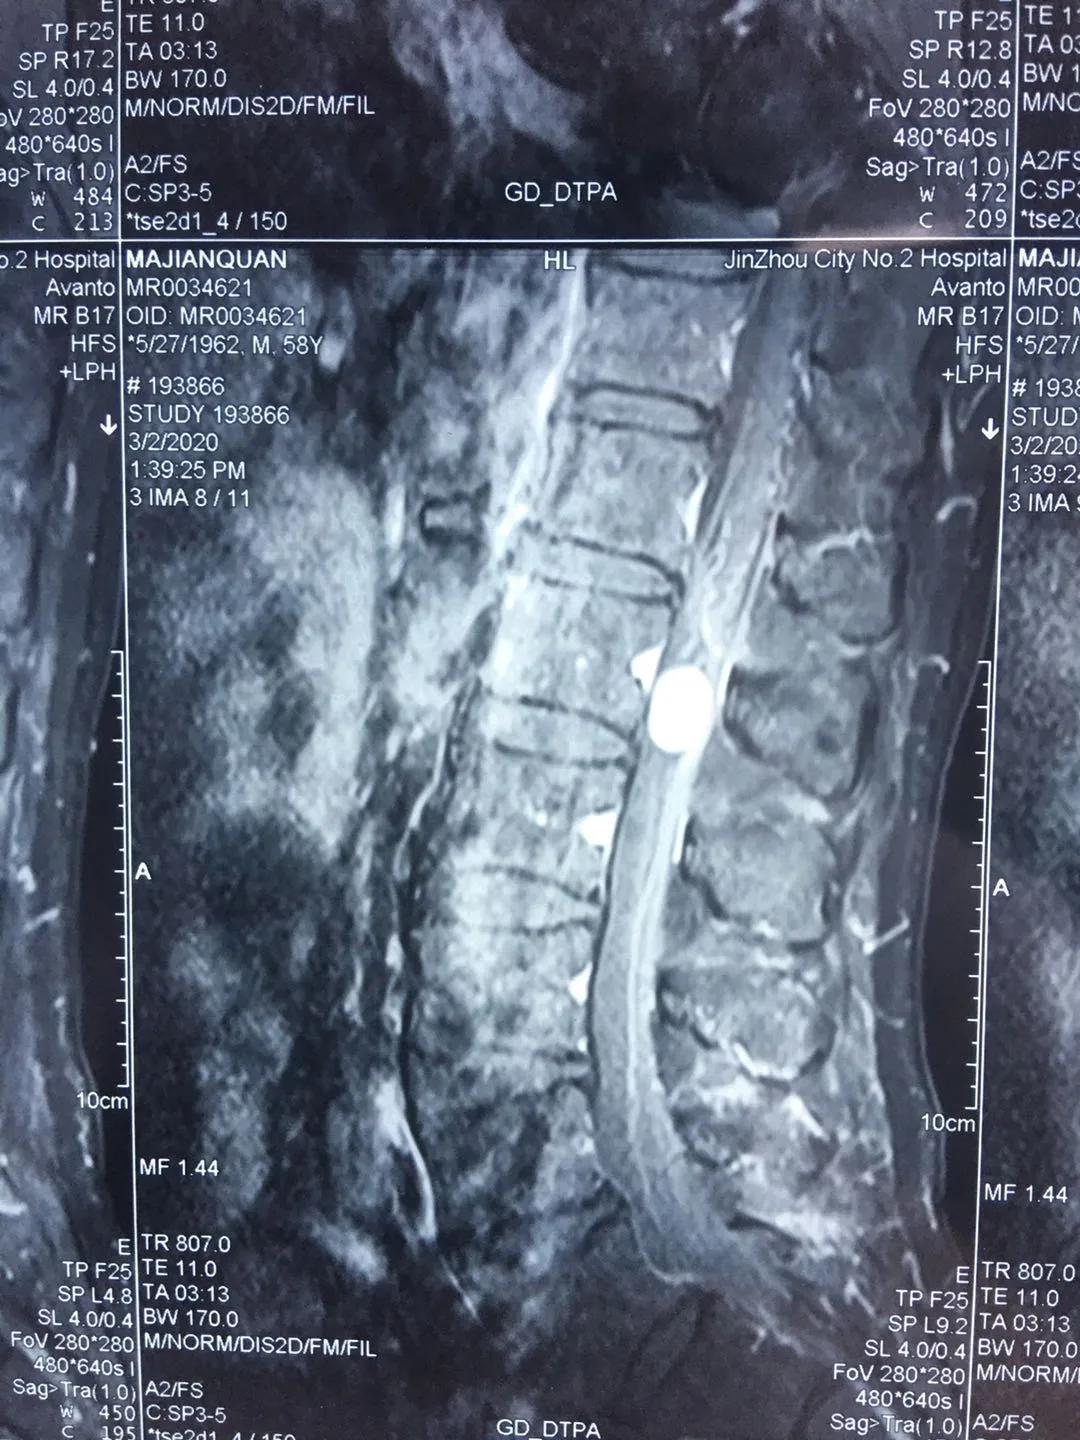

患者马先生今年58岁,于2年前无明显诱因出现左下肢抽痛,呈间歇性发作,以双下肢后明显,行走时有针刺样疼痛,伴双下肢麻木不适,2个月前马先生上述症状加重,行脊柱MRI平扫+增强提示腰椎管内肿瘤,神经鞘瘤可能性大,患者慕名来到市二院骨八科找到田晓东博士,请求田晓东博士为他解除痛苦。

经骨八科田晓东主任及神经外科黄涛主任等医务人员讨论认为:患者手术指征明确,并无明显手术禁忌,建议尽快行手术治疗。手术拟行腰椎后路切开椎弓根钉棒系统内固定+椎板切除+腰椎管内肿瘤切除术联合手术治疗。术后,患者症状改善明显,双下肢抽搐痛伴麻木症状逐渐改善,肢体力量也逐渐恢复。